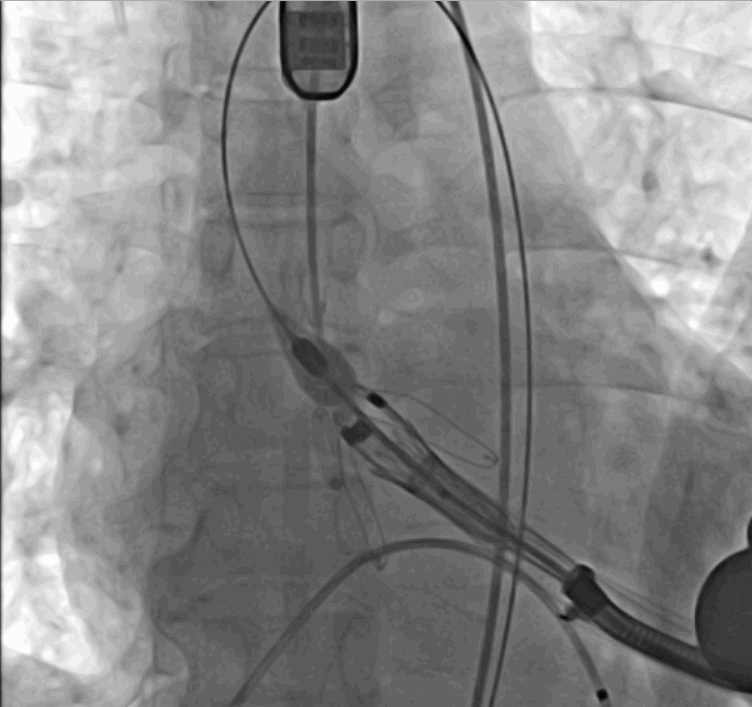

術(shù)中瓣膜釋放過(guò)程

手術(shù)采用經(jīng)心尖入路,對(duì)患者進(jìn)行全麻后,在左側(cè)心尖處做3-4cm微創(chuàng)手術(shù)切口,在DSA及超聲引導(dǎo)下手術(shù)順利完成。從導(dǎo)入器械到完成瓣膜置入,僅耗時(shí)約10分鐘。術(shù)后即刻主動(dòng)脈瓣返流程度由術(shù)前大量返流轉(zhuǎn)為消失,患者于導(dǎo)管室拔除氣管插管,次日由ICU轉(zhuǎn)入普通病房。